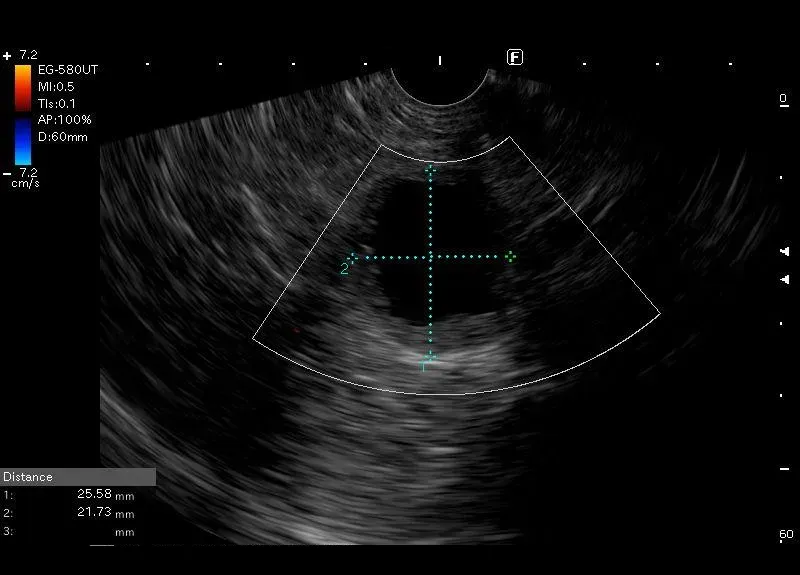

Widoczna w ogonie trzustki zmiana o morfologii grubościennej torbieli z przyściennymi elementami litymi, bez przepływu w opcji power doppler i pogrubieniem ściany do 4mm, otoczona niewielkim rąbkiem halo.